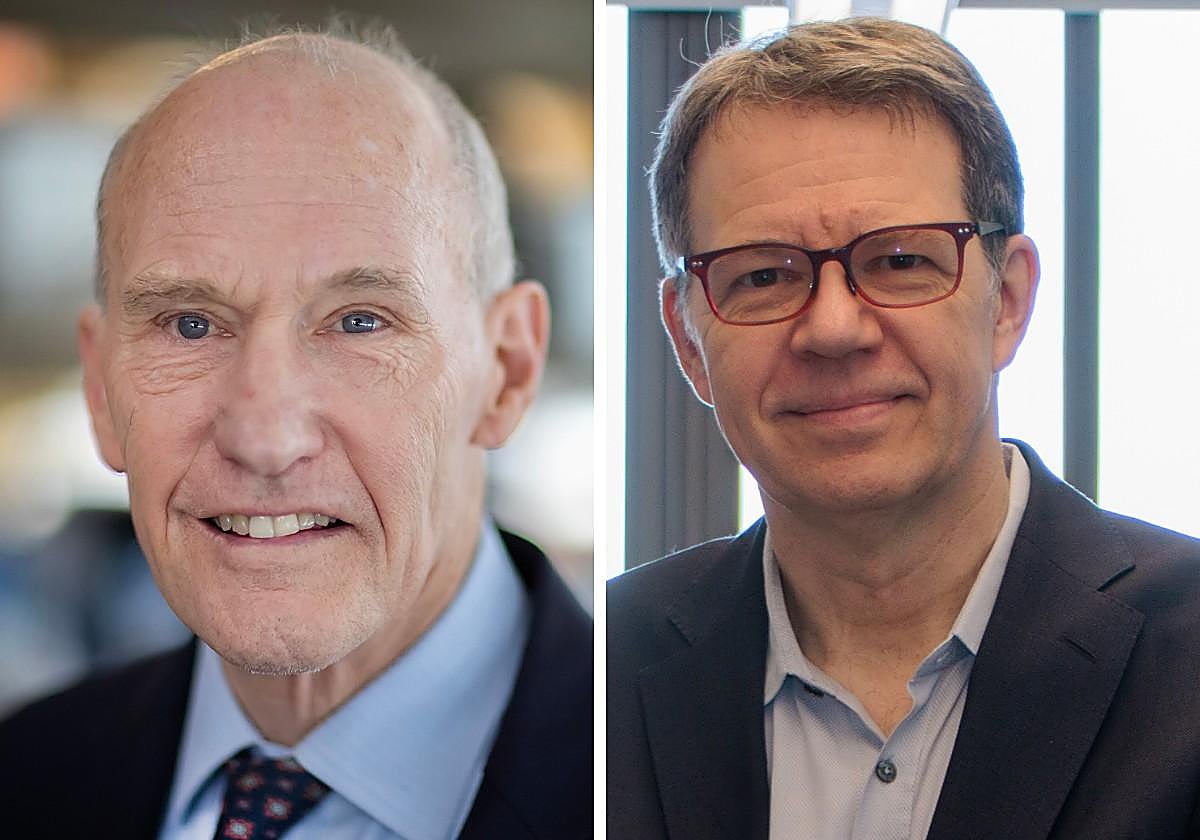

Los padres de la terapia CAR-T, Carl June y Michel Sadelain, han sido galardonados con el Premio Fronteras por su trabajo en una de las técnicas más prometedoras en la lucha contra el cáncer. Esta terapia se basa en la modificación genética de linfocitos T del propio paciente, convirtiéndolos en verdaderos «soldados» capaces de identificar y eliminar células cancerosas.

La terapia CAR-T fue desarrollada a partir de trabajos previos, incluyendo los realizados por el investigador israelí Zelig Eshhar en 1993. Sadelain logró demostrar su viabilidad en 2002, superando los desafíos iniciales que hacían que los linfocitos T murieran al ser reintroducidos en el organismo. Sin embargo, el camino hacia la aplicación clínica de esta terapia fue impulsado por la tragedia personal de Carl June, quien perdió a su primera esposa por cáncer de ovario. «Esta nueva estrategia terapéutica se convirtió en una prioridad para mí», afirma June.

En 2010, June llevó a cabo ensayos clínicos con los primeros pacientes terminales de leucemia, obteniendo resultados superiores a los alcanzados en modelos animales. Este éxito llevó a la aprobación en 2017 de la primera terapia CAR-T en Estados Unidos, destinada a niños y adultos jóvenes con leucemias agudas refractarias, así como a algunos tipos de linfomas. Un año más tarde, la Agencia Europea de Medicamentos autorizó su uso en la Unión Europea.